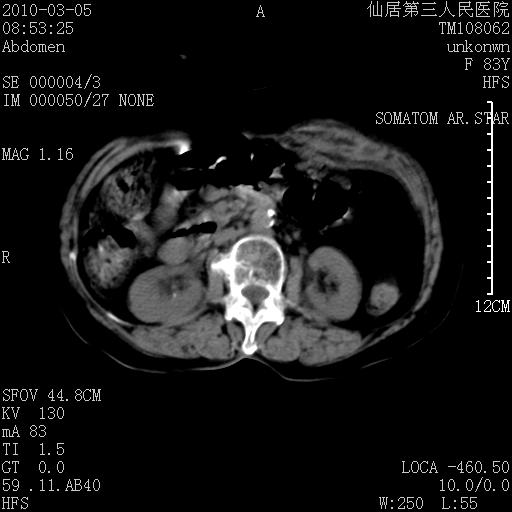

标题: CT24879:腹直肌病变。在线等。 [打印本页]

标题: CT24879:腹直肌病变。在线等。

女性,83y,腹痛一周。

考虑:左侧腹直肌神经纤维瘤可能

神经纤维瘤—伴有出血?

有无外伤,血肿或韧带样瘤

考虑左侧腹直肌血肿,肿瘤性病变待排。

增强看看,mfh可能性大,次之可考虑血肿、bfh、转移瘤、神经纤维瘤、侵袭性韧带样纤维瘤等。肝内钙化灶,右肾结石。

支持血肿

支持腹壁纤维肉瘤

血肿,纤维瘤,子宫内膜异位都有可能。